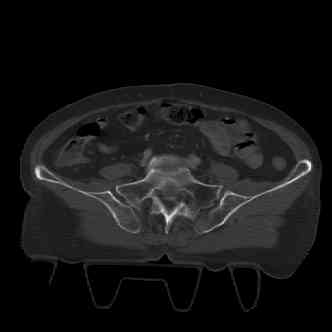

attached are several CT cuts. please let me know if you need more. the CT is pre-pelvic ex-fix placement.

Имя     : image001.jpg